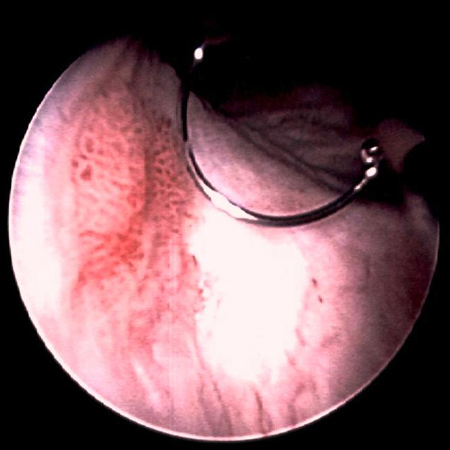

[Figure caption and citation for the preceding image starts]: Carcinoma urotelial de baixo grau disseminado na uretra prostática; a ilustração mostra o eletrodo de alça usado para remover tumores de bexigaDo acervo de Donald Lamm, MD, FACS [Citation ends].

[Figure caption and citation for the preceding image starts]: Carcinoma in situ da bexiga; pode parecer uma mancha eritematosa áspera na bexiga, mas o urotélio costuma parecer normal; a biópsia aleatória ou biópsia das áreas tingidas com azul de metileno a 0.2%, ilustrada aqui, é necessária para fazer o diagnósticoDo acervo de Donald Lamm, MD, FACS [Citation ends].